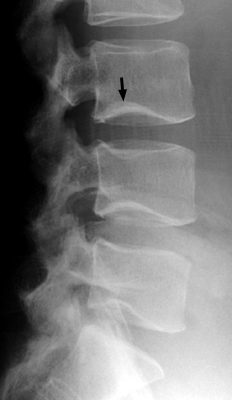

Frontal and lateral radiograph of the lumbar spine with curvature of the inferior endplate of the 4th and 5th lumbar vertebrae, which mimics the curvature of Cupid's bow aimed cephalad. The unusual, non-flat surface of the inferior endplate is a normal variant, and need not be misinterpreted as inherent osseous abnormality or adjacent pathological process.

- Click on the image for a larger versionA - Click on the image for a larger versionB